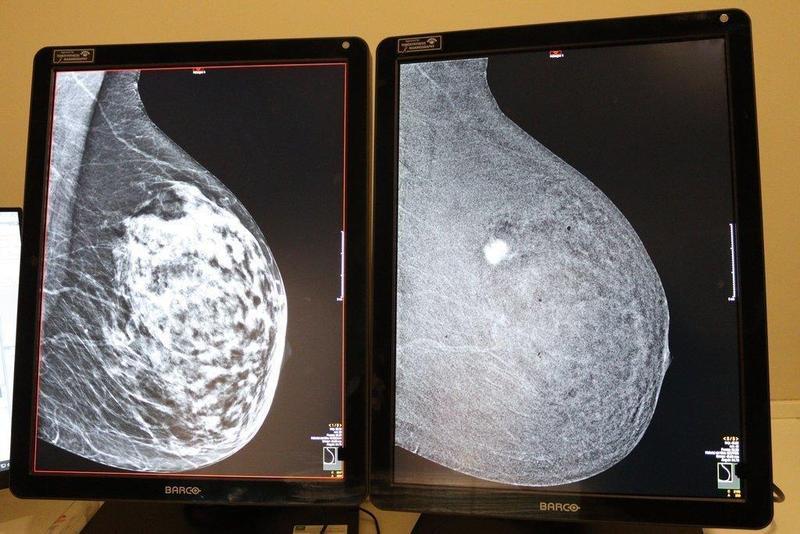

Diferencia entre mamografía convencional (izquierda) y con contraste (derecha).